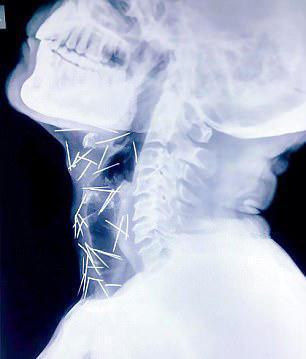

男子的全身都插满了钢针,后来仔细确认总共有75根钢针,其中40根在喉咙上,还有25根在右腿,其余的钢针在手臂上。

不过幸运的是钢针没插在内脏上,因此男子暂时保住自己一命,但是当地的医院都拒绝为他取钢针,男子只好等待找到合适的意愿,躺在病床上。